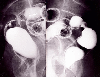

Type 3 (ulcerated type with infiltration) advanced rectal cancer showing a relatively shallow crater formation and the mucosal folds with convergence at the marginal area

Tokyo Pref., Cooperative study between National Cancer Center and Kyushu Cancer Center

Malignant epithelial tumor/Adenocarcinoma